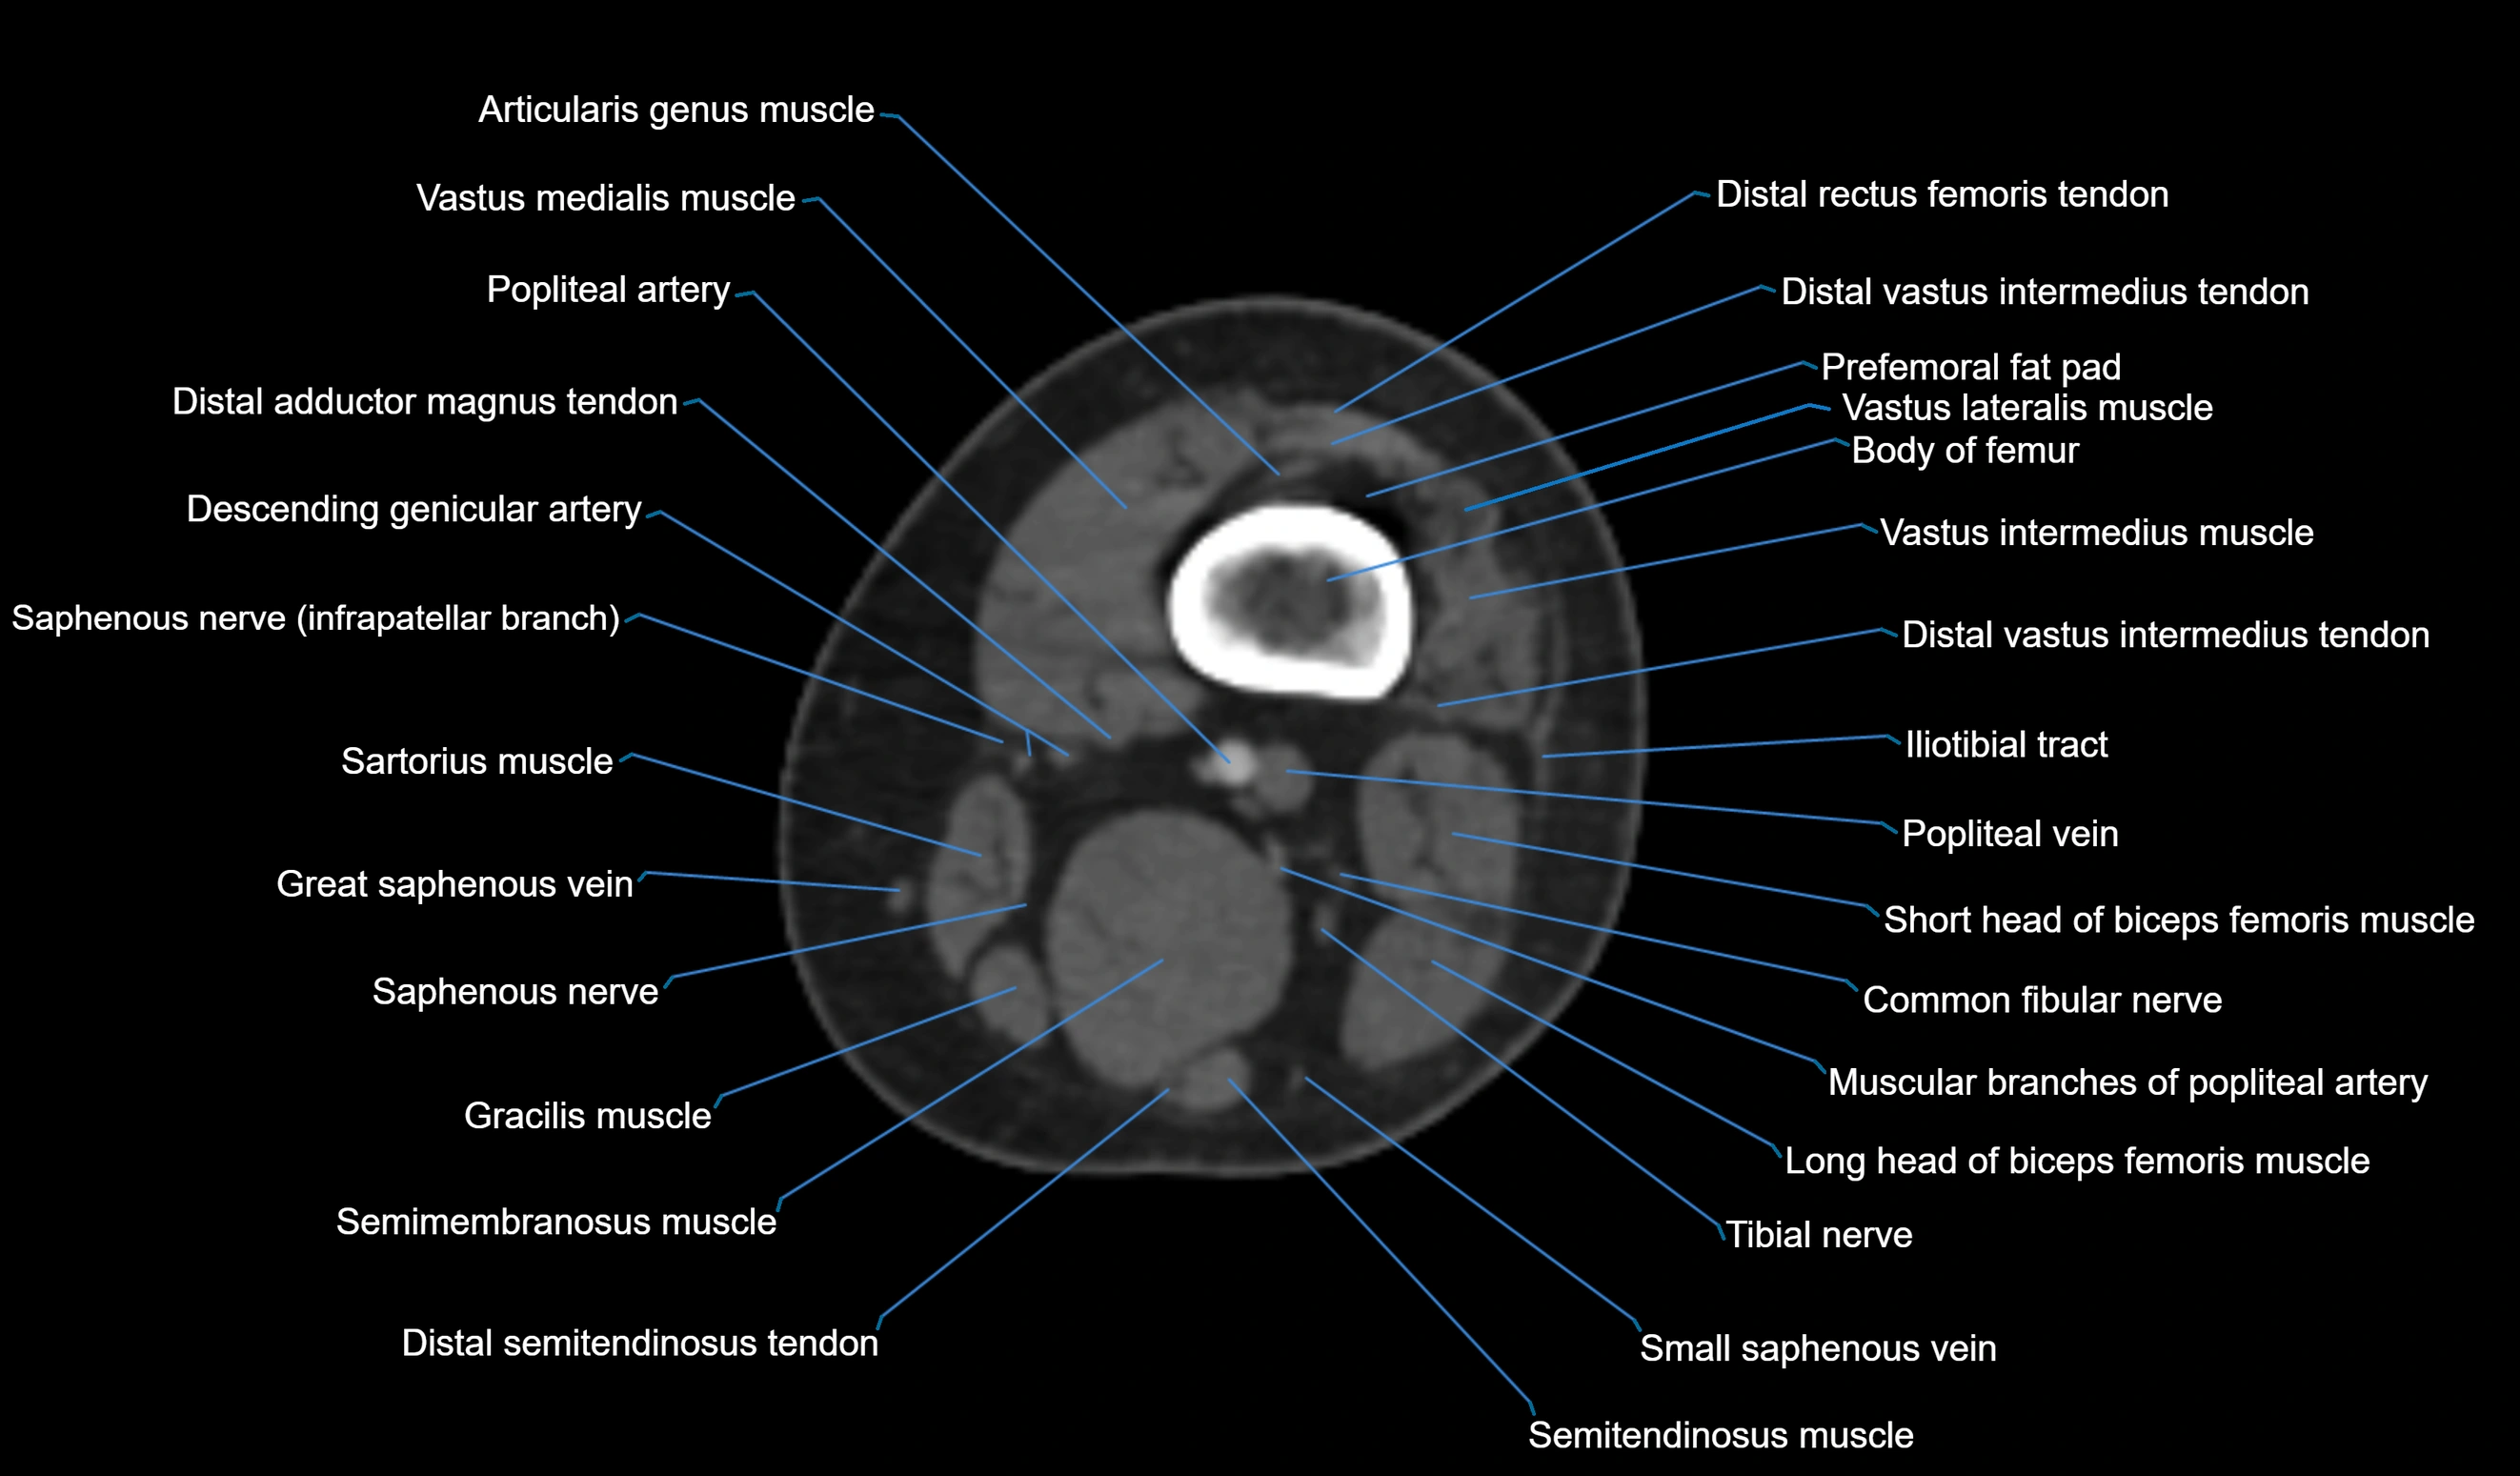

- Biceps femoris muscle (Long head)

- Biceps femoris muscle (Short head)

- Body of femur

- Common fibular nerve

- Distal adductor magnus tendon

- Distal rectus femoris tendon

- Distal semitendinosus tendon

- Distal vastus intermedius tendon

- Popliteal artery

- Popliteal vein

- Prefemoral fat pad

- Saphenous nerve

- Sartorius muscle

- Semitendinosus muscle

- Small saphenous vein

- Tibial nerve

- Vastus lateralis muscle

- Vastus medialis muscle

- great saphenous vein